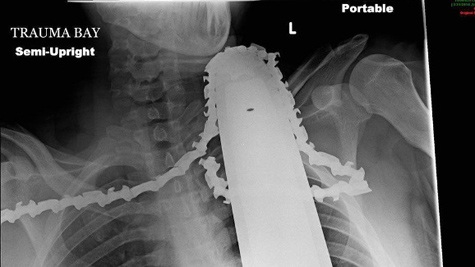

Hình ảnh X-quang chiếc lưỡi cưa ăn sâu vào cổ và vai của nạn nhân (ảnh: AP)

Động cơ được tháo khỏi máy cưa nhưng lưỡi cưa vẫn được để nguyên ở cổ để đề phòng mất máu.

Nhân viên cấp cứu đã gỡ động cơ khỏi chiếc cưa nhưng vẫn để lưỡi cưa ở cổ và vai của Valentine nhằm ngăn ngừa mất máu thêm, giám đốc đơn vị điều trị tích cực của bệnh viện cho hay.